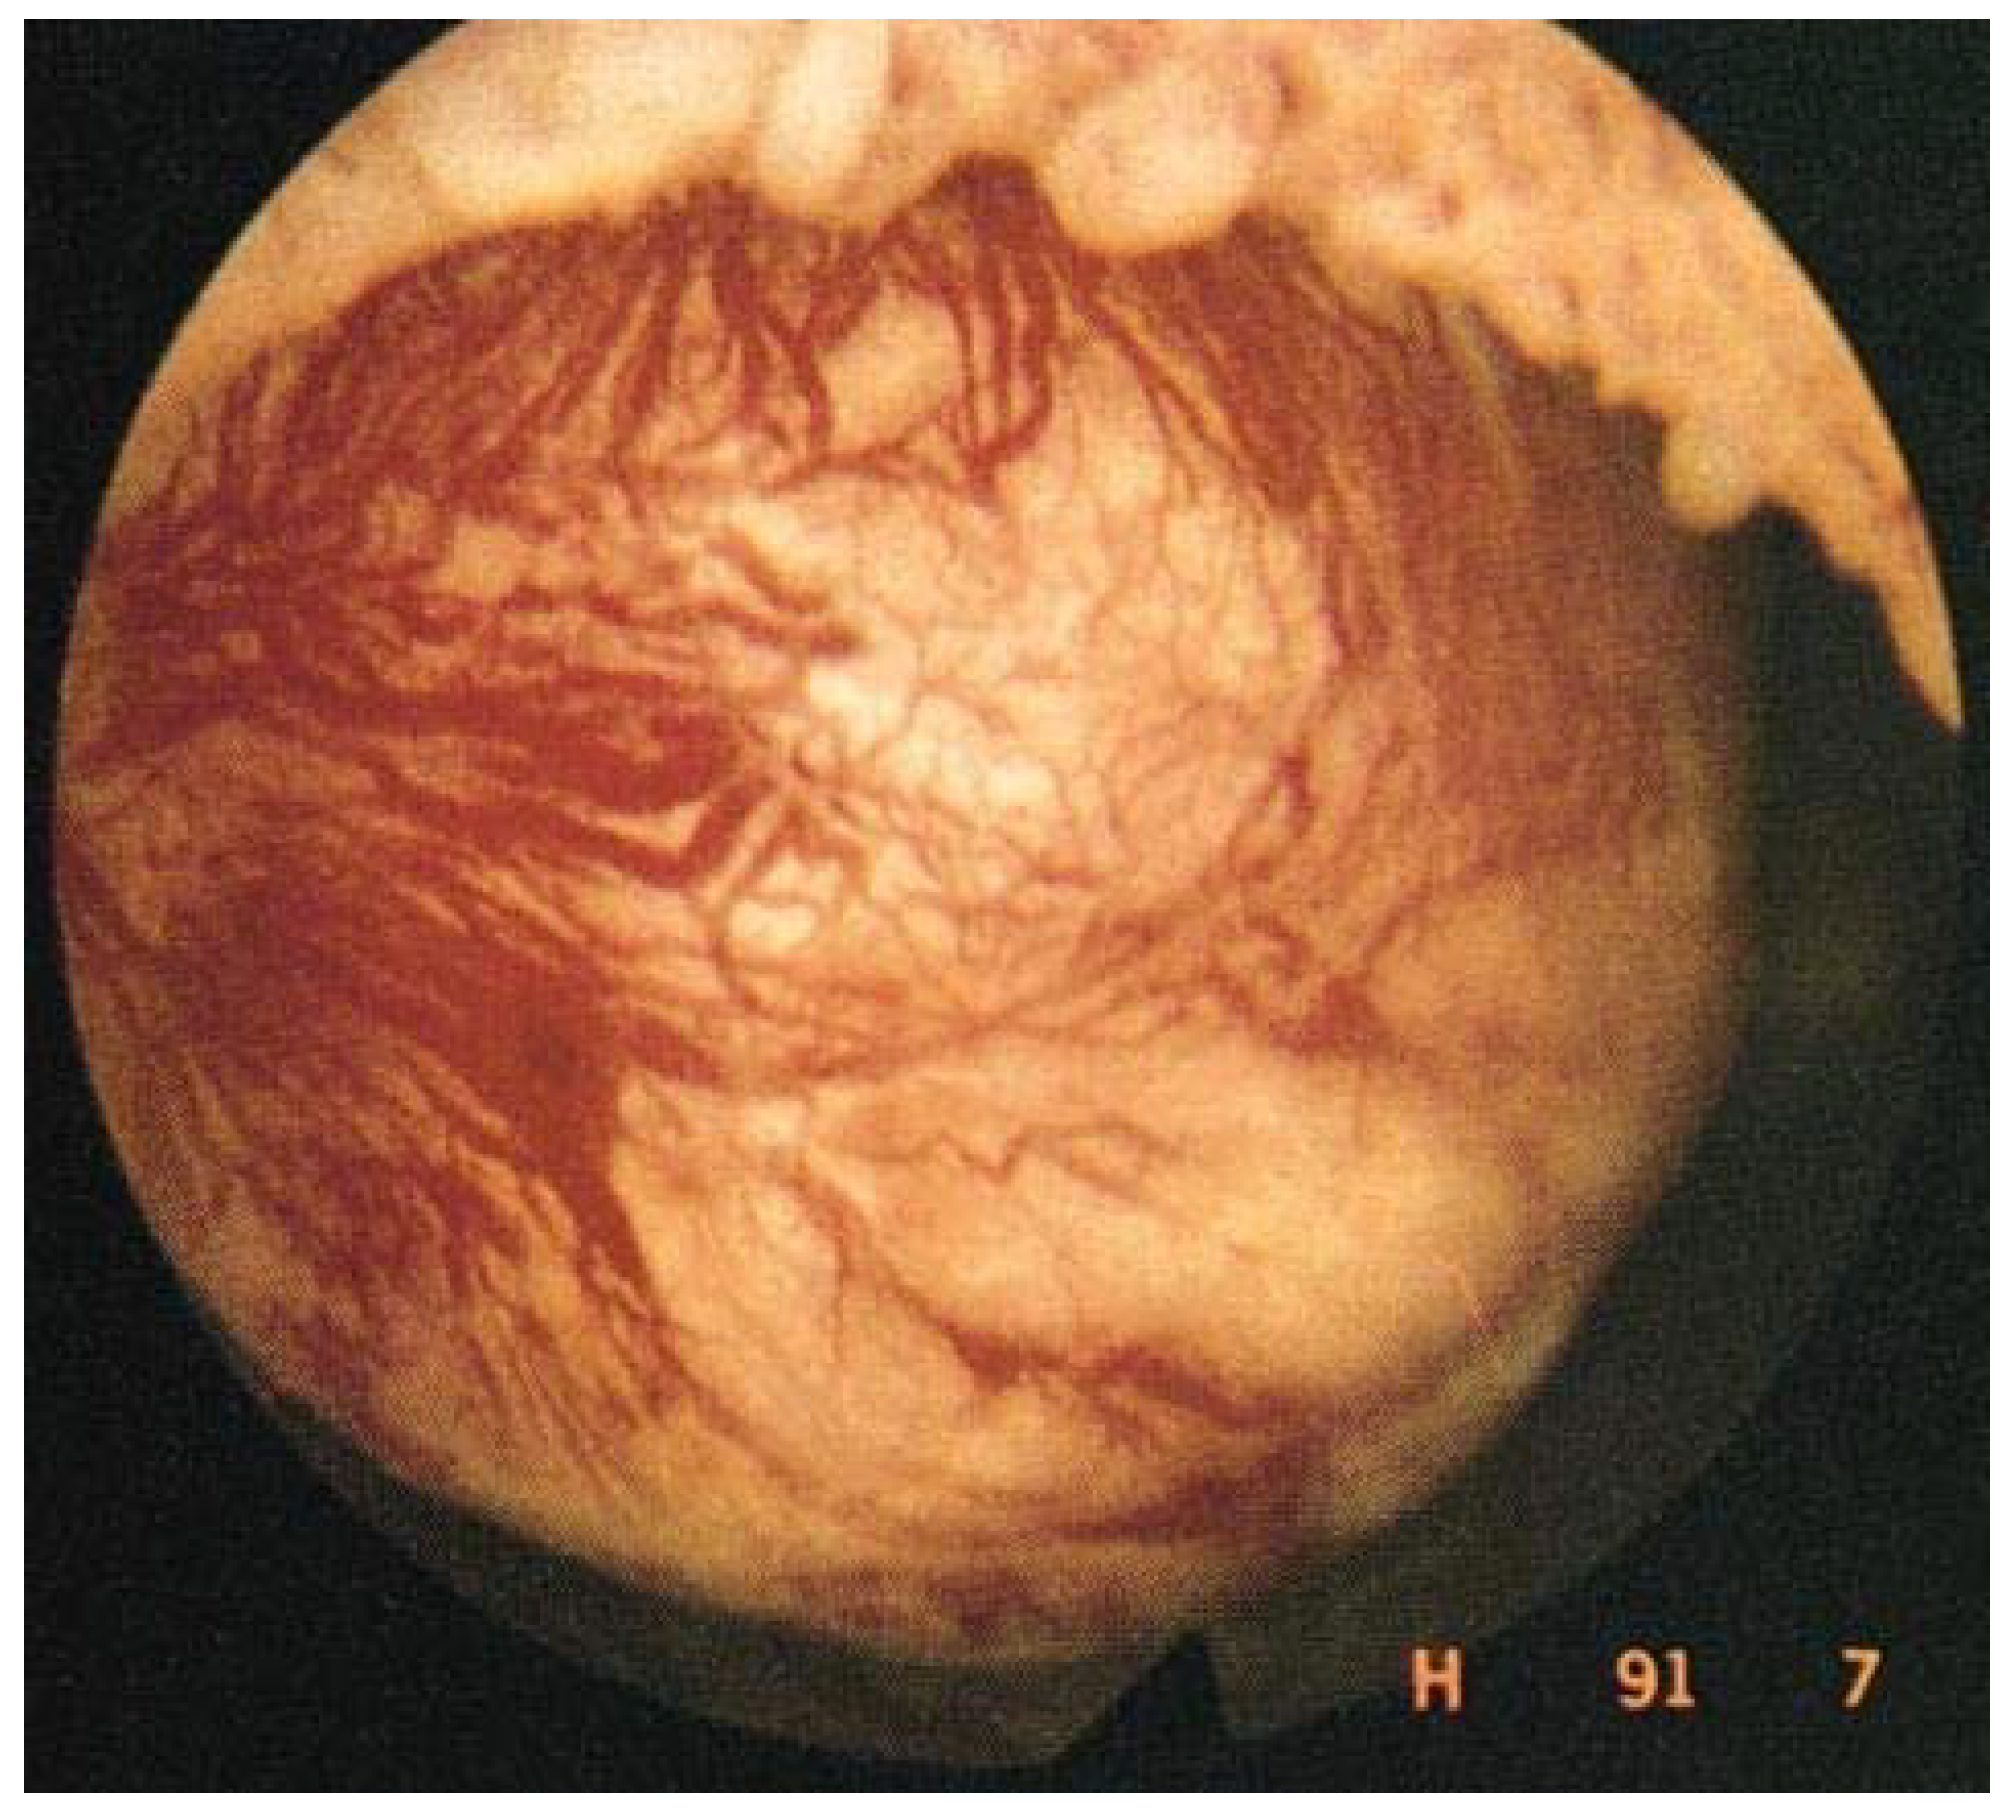

5.6. GnRH Antagonists

Data from phase 3 clinical trials investigating oral GnRH antagonists (elagolix, relugolix, linzagolix) are now available [5,56,57,58,59,60]. Subjects received GnRH antagonist with add-back therapy [ABT] (1 mg estradiol + 0.5 mg norethisterone acetate). The results demonstrated excellent control of fibroid-related HMB and showed the reduction in bleeding to be maintained when ABT was associated, curbing BMD loss. Indeed, more than 70% of participants met the primary endpoint (menstrual blood loss <80 mL and >50% reduction from baseline) (Figure 5) and over 50% were amenorrheic [5].

Figure 5. Percentage of women meeting the primary endpoint (those with menstrual blood loss of less than 80 mL and at least 50% down from baseline) in patients treated by a GnRH antagonist combined with add-back therapy (ABT) in the first and second clinical trial respectively (300 mg elagolix twice daily + ABT (Elaris 1 and 2); 200 mg linzagolix once daily + ABT (Primrose 1 and 2); 40 mg relugolix once daily + ABT (Liberty 1 and 2)).

The decline in fibroid volume was, however, found to be more limited in subjects with ABT than without ABT. Indeed, Osuga et al. clearly demonstrated that 40 mg/day relugolix decreases fibroid volume by more than 50% after 24 weeks of treatment [57]. Steward et al. also concluded that 200 mg linzagolix reduces fibroid volume more efficiently than linzagolix + ABT (Figure 6 and Figure 7) [60]. Further studies are nevertheless needed to identify the best protocol and dose to use if reducing myoma volume is the intended goal, as in the case of myoma-related infertility.

Figure 6. Fibroid volume reduction: 200 mg linzagolix and 40 mg relugolix significantly reduce myoma volume (p < 0.001). The decrease was not significant when ABT was added.

Figure 7. Significant reduction in myoma and uterine volume after 12 weeks of 200 mg/day linzagolix. At baseline, volume was estimated to be 396 cm3. After 12 weeks of treatment, it dropped to 169 cm3.